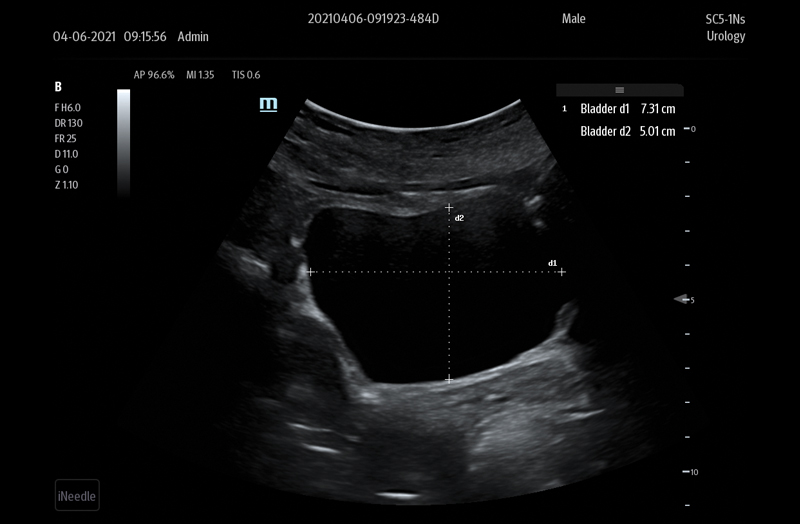

The TE7 Max Ultrasound System is designed to maximize your capabilities in demanding Point of Care environments. With its thoughtful industrial design and best-in-class image quality, the

TE7 Max provides a superior user experience during rapid clinical assessments and procedures taking place at the patient’s bedside

or on the go.

The TE7 Max boasts a large 21.5” vertically oriented high-definition display and a sealed touch-based interface to optimize visualization and accessibility when every second counts. The TE7 Max also incorporates a comprehensive suite of artificial intelligence (AI) powered Smart Tools and workflow enhancement software (iWorks™ Protocol) making efficiency and reproducibility the expectation for all end users.